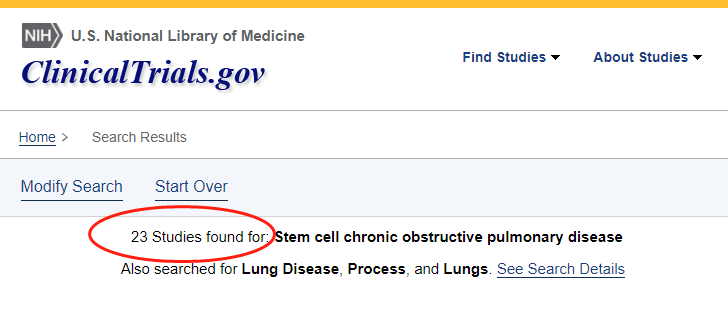

干細胞治療慢阻肺臨床進展

截止目前,國際上在clinicaltrials.gov系統中注冊的干細胞治療慢性阻塞性肺疾病的臨床研究項目有23個,其中9項顯示已完成(complete)。?